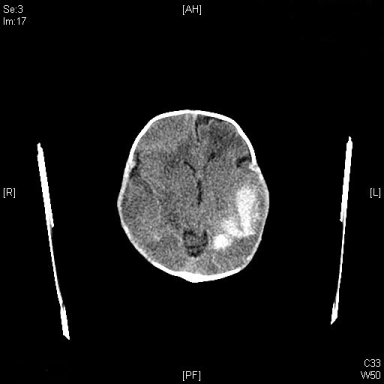

The author reports a case of fetal intracranial hemorrhage diagnosed at 36 week of gestation for primigravida confirmed postnatally with both neonatal head ultrasound and CT scan. Subsequent head CT scan repeated as a follow up which showed dramatic improvement and regression of the ICH with normal clinic examination and no brain squeal. A 38-year-old, Gravida 1 known case of Essential Hypertension on medication and Aspirin. She was diagnosed with gestational diabetes as well her blood sugar readings values were under control on diabetic diet. There was no history of trauma or fall during or infection during her pregnancy. Her antenatal screening test was all in normal values. TORCH panel was non-reactive. Blood group is O positive with negative antibodies. Her first fetal ultrasound done at 22 weeks and 2 days of gestation with normal morphology and fetal biometry. A follow up fetal wellbeing ultrasound repeated at 36 weeks of gestation with the following findings, single viable fetus, cephalic in presentation, normal growth for gestational age. Amniotic fluid volume polyhydraminous Amniotic Fluid Index 33.8 cm. The abnormal finding in fetal head a noted presence of a mixed echogenic intracranial mass, measuring 4 × 7 cm with irregular margins occupying the left temporoparietal lobe compressing the posterior horn of left lateral ventricle with no element of midline shift mild bilateral ventriculomegaly noted. No other structural anomaly noted and nor element of fetal hydropes (Figure 1).

Figure 1: Sonographic demonstration of intracranial hemorrhage at 36 weeks of gestation, an axial view of fetal head showing a mixed echogenic intracranial collection measuring 4 × 7 cm with irregular margins occupying at the left temporo-parietal lobe compressing the posterior horn of left lateral ventricle with no element of midline shift. View Figure 1